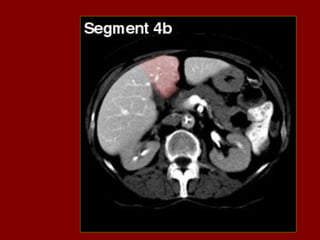

REVISÃO ANATOMIA

SECCIONAL

ABDOME